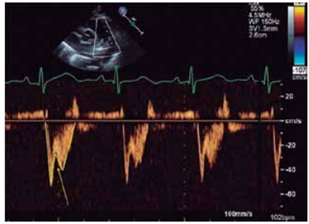

Ao realizar-se ecocardiograma transesofágico, nota-se a

imagem a seguir.

(GOLDSTEIN, S. A. et al. ASE’s Comprehensive Echocardiography. 2nd edition. Elsevier Health Sciences, 2016)

As setas superior e inferior indicam respectivamente: